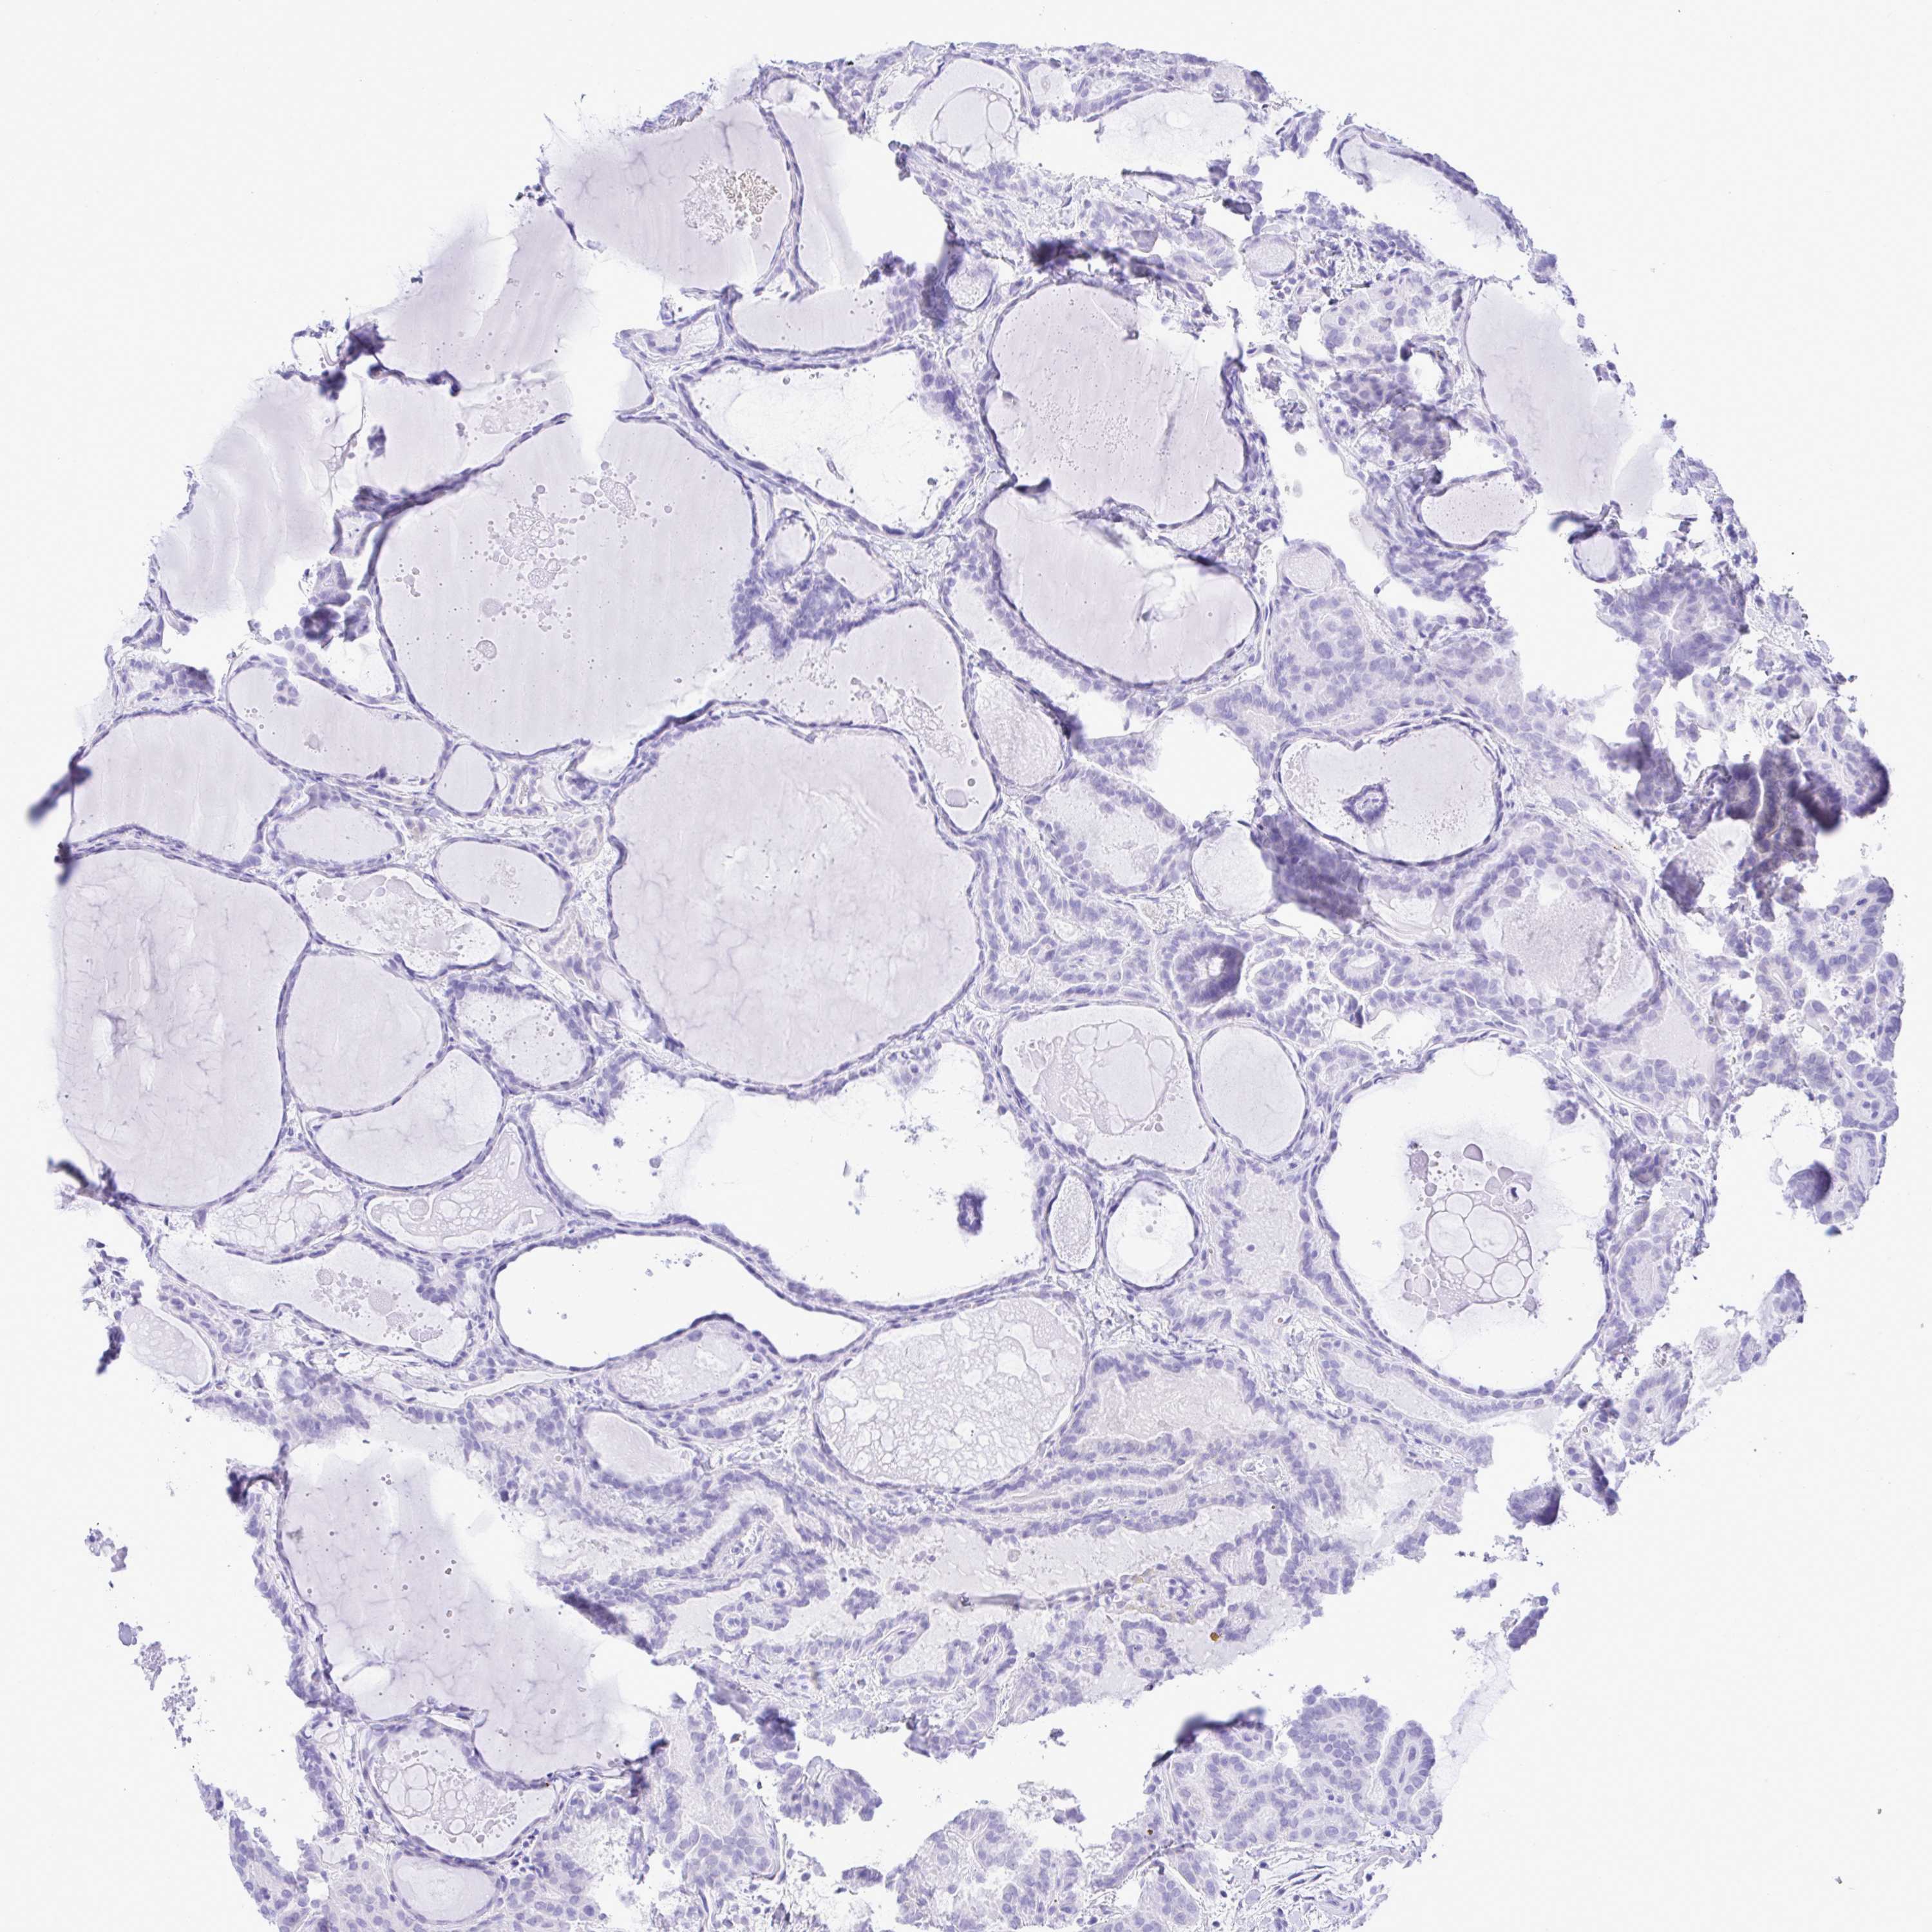

THYROID CANCER - Protein expressioni

A mouse-over function shows sample information and annotation data. Click on an image to view it in a full screen mode. Samples can be filtered based on level of antibody staining by selecting one or several of the following categories: high, medium, low and not detected. The assay and annotation is described here.

Note that samples used for immunohistochemistry by the Human Protein Atlas do not correspond to samples in the TCGA dataset.

Antibody stainingi

Antibody staining in the annotated cell types in the current human tissue is reported as not detected, low, medium, or high, based on conventional immunohistochemistry profiling in selected tissues. This score is based on the combination of the staining intensity and fraction of stained cells.

Each image is clickable and will lead to virtual microscopy that enables deeper exploration of all samples and also displays staining intensity scores, fraction scores and subcellular localization as well as patient and tissue information for each sample.

Antibody HPA059274

Staining

High

Medium

Low

Not detected

Intensity

Strong

Moderate

Weak

Negative

Quantity

>75%

75%-25%

<25%

None

Location

Nuclear

Cytoplasmic/membranous

Cytoplasmic/membranous,nuclear

Papillary adenocarcinoma, NOS

Follicular adenoma carcinoma, NOS